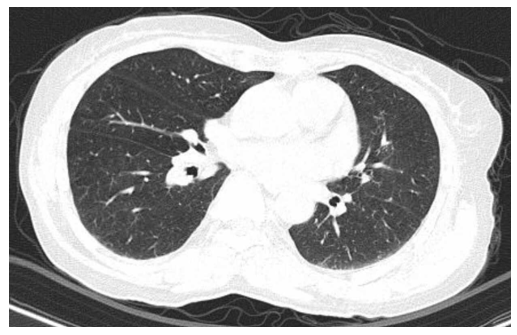

Hình 9: Chụp CT lồng ngực có tiêm thuốc cản quang sau điều trị không phát hiện hình ảnh nghi ngờ thứ phát.